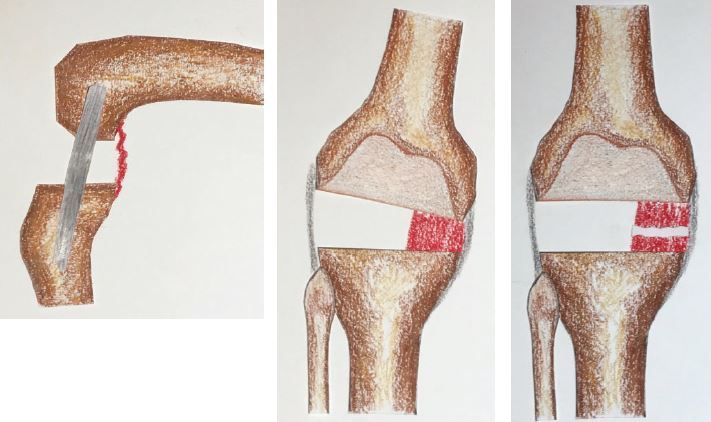

Key Points: The methodology is based on the premise that the superficial MCL is often tented by osteophytes rather than contracted. Preoperative and intraoperative assessments must identify extra-articular deformities (EAD) and hindfoot valgus, which influence the weight-bearing axis. Following bone resections perpendicular to the mechanical axes, three clinical scenarios guide soft tissue management. Symmetrical gaps require no further release. If the extension gap is tight medially but the flexion gap is symmetrical, a posteromedial capsular release or a sliding medial condylar osteotomy is indicated. If both gaps are tight medially, a reduction osteotomy of the posteromedial tibial flare is performed, followed by semimembranosus release or corrective metaphyseal osteotomy if EAD is present.

Scenario 3:

- Extension gap tight medially

- Flexion gap tight medially

- Reduction osteotomy3 of the posteromedial tibial flare helps to achieve correction by reducing the tenting of the MCL

- If a trapezoidal gap persists it implies severe contracture of posteromedial structures and semimembranosus. So the next step is to resect a segment of the posteromedial capsule and release the semimembranosus from its tibial attachment

- If these are released and deformity persists, it implies that there is a tibial EAD. This should have been detected and anticipated in the planning stage. Obtain a rectangular extension gap by re-cutting proximal tibia. Any residual varus deformity is corrected by closed-wedge osteotomy at apex of deformity usually in the tibial metaphysis.